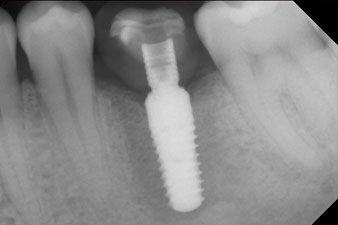

After healing of the soft tissue, the implant stability was measured again before delivery of the prosthetic restoration.

Both values were virtually unchanged and were between the medium and the high range – where the lower value is always used as the reference value that determines the treatment.

Therefore, successful osseointegration and adequate biological stability could be recorded, which enabled an impression to be taken in the same session.

The final pictures show the screw-retained monolithic composite crown in place and the x-ray check (Fig. 9 and 10) (6).